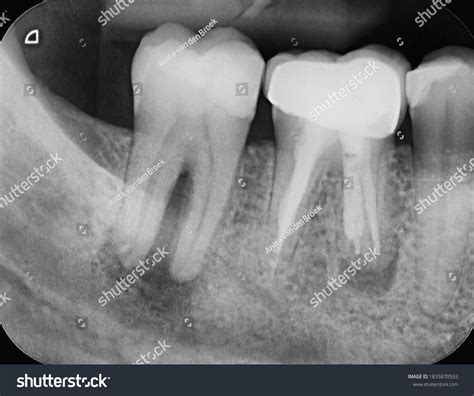

1. Diagnosis: Digital X-rays are taken to visualize the infection.

The progression from minor decay to a full-blown teeth root canal infection usually occurs in stages. Initially, bacteria enter the tooth's interior through a compromised enamel layer. Once inside the pulp chamber, these bacteria multiply, causing inflammation. As the pulp dies, toxins can escape through the tip of the tooth root and enter the surrounding bone, potentially forming an abscess.